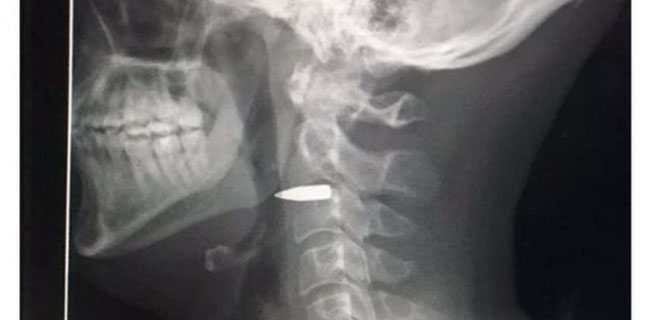

Hasil X-ray Adam Harvey/Twitter

Harvey memasang gambar sinar X-ray yang menunjukkan bahwa ada sebuah peluru yang bersarang di lehernya.

Dikabarkan BBC, ia kemudian mendapat pertolongan pertama dari rekan-rekan di tempat kejadian. Mereka sempat mengira dia terkena pecahan peluru, tapi ketika dia mencari perhatian medis, gambar sinar-X itu membuatnya jelas bahwa dia terkena peluru.

"Untungnya itu melewati segala sesuatu yang penting dan baru saja tersangkut di balik rahang saya," katanya.

Dia tidak kehilangan kesadaran dan disarankan memakai penjepit leher sebagai tindakan pencegahan.